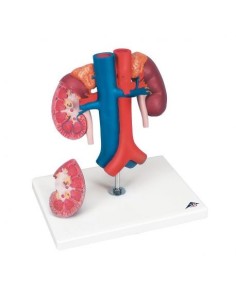

Dal cranio in 22 parti con incastri magnetici ai modelli di colonna vertebrale, da quelli di articolazioni a quelli di cuore, ogni pezzo della nostra collezione è progettato per un’immersione totale nello studio dell’anatomia umana. I nostri modelli, realizzati tramite scansioni di ossa vere, garantiscono un’esperienza tattile autentica e una fedeltà di peso quasi identica agli originali.

Essenziali per studenti e professionisti, i nostri modelli anatomici sono strumenti didattici che permettono di osservare le strutture anatomiche con precisione, eliminando la necessità di dissezioni o studi invasivi. Sono inoltre utili per spiegare ai pazienti le patologie, rendendo la comunicazione più efficace e risparmiando tempo prezioso.